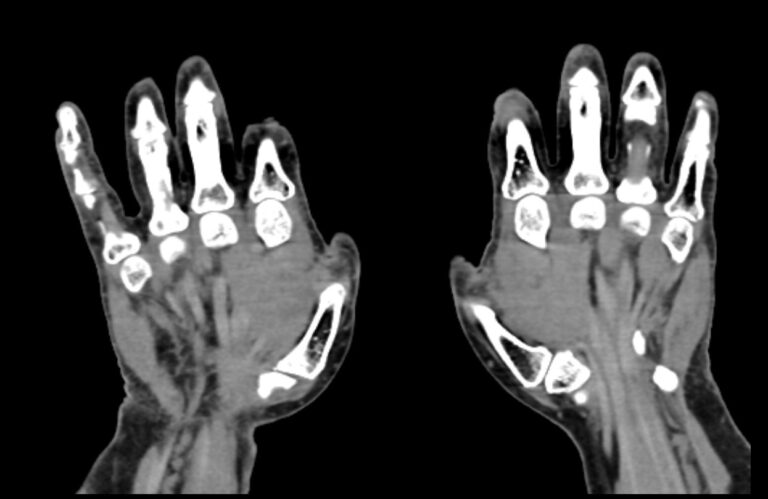

Мультиспиральная компьютерная томография является наиболее точным и информативным методом диагностики травматических повреждений и различных заболеваний костей и суставов пальцев рук. КТ относится к лучевым методам обследования, то есть основан на применении рентгеновского излучения. Быстрота выполнения, неинвазивность (не нужно вмешательство в организм), доступная стоимость делают это исследование незаменимым в травматологии и ортопедии. С помощью КТ проводится диагностика вывихов, ушибов, переломов костей пальцев руки.

При помощи проникающей способности рентгеновских лучей томограф производит послойное сканирование исследуемой области. В результате получаются детальные снимки, а после цифровой обработки данных – подробные трехмерные изображения кисти и пальцев руки.

В наших медицинских центрах КТ пальцев рук выполняется на новейших мультиспиральных компьютерных томографах экспертного уровня TOSHIBA AQUILION. Современное оснащение аппаратов позволяет получать детальные изображения высокого уровня четкости и контрастности, что обеспечивает точность и достоверность диагностики. При этом за счет скоростного мультисрезового сканирования пациент получает уменьшенную дозу рентгеновского облучения.